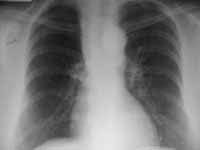

En los casos en los cuales se presenta una atelectasia completa de un lóbulo pulmonar, el otro lóbulo en el lado izquierdo o los otros dos en el derecho pueden presentar hiperlucencia con aparente disminución del flujo sanguíneo.(Figura 4).

Figura 4. Atelectasia LSD. Hiperlucencia LM y LID.